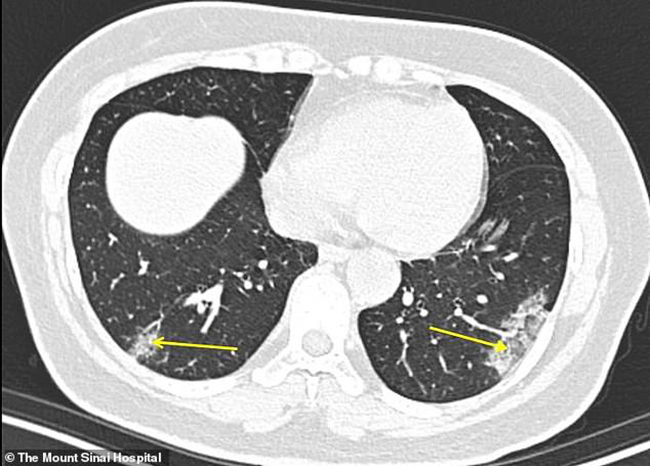

Những bệnh nhân được quét từ 0 đến 2 ngày sau khi các triệu chứng xuất hiện lần đầu tiên có rất ít hoặc không có triệu chứng về bệnh phổi. Ảnh chụp CT của bệnh nhân 19 tuổi, 1 ngày sau khi các triệu chứng xuất hiện. (Ảnh: Dailymail)

Chụp CT ngực của một người đàn ông 34 tuổi bị coronavirus ở Trung Quốc. Một nửa trong số những bệnh nhân nhiễm Covid-19 trong 2 ngày đầu tiên không có những triệu chứng rõ rệt ở phổi. (Ảnh: Internewscast)